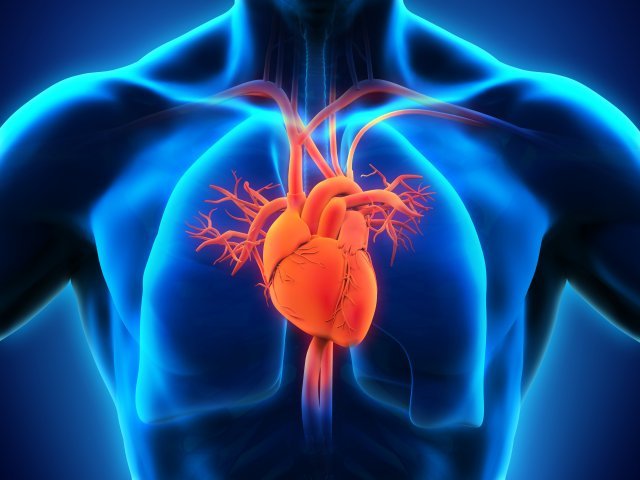

గుండెకు సంబంధించిన ధమనుల్లో కొవ్వు పదార్ధాలు పేరుకుని పోవడంతో వచ్చే జబ్బును అథెరోస్కిరోసిస్ అని అంటారు. ప్రపంచం మొత్తం మీద వచ్చే గుండెజబ్బుల రోగుల్లో మూడోవంతు మరణాలకు ఇదే కారణంగా పరిశోధనల్లో వెల్లడైంది. ఇది కాక, బ్లడ్ కొలెస్టరల్, మాంద్యం, చురుకుదనం లోపించడం, వయోభారం, రక్తపోటు, ఊబకాయం, పొగతాగడం ఇవన్నీ కూడా గుండెజబ్బులకు కారణమవుతున్నాయి.

ఏదెలా ఉన్నా గుండెజబ్బులకు (కార్డియో వాస్కులర్ డిసీజ్) సంబంధించిన సంఘటనలు అథెరోస్క్లిరోసిస్ వల్లనే 15 శాతం వరకు ఉంటున్నాయని పరిశోధకులు వివరించారు. మానవుల్లో ఇది సహజంగా కనిపించినా, చింపాంజీ వంటి మానవ లక్షణాలతో సంబంధం ఉన్న క్షీరదాల్లో ఇటువంటి వ్యాధి లక్షణాలు కనిపించవని దశాబ్దం క్రితం వరకు అనుకునేవారు. కానీ చింపాంజీల్లో గుండె కండరాలు దెబ్బతినడం వల్ల అథెరోస్కిరోసిస్ వస్తోందని అధ్యయనంలో తేలింది.